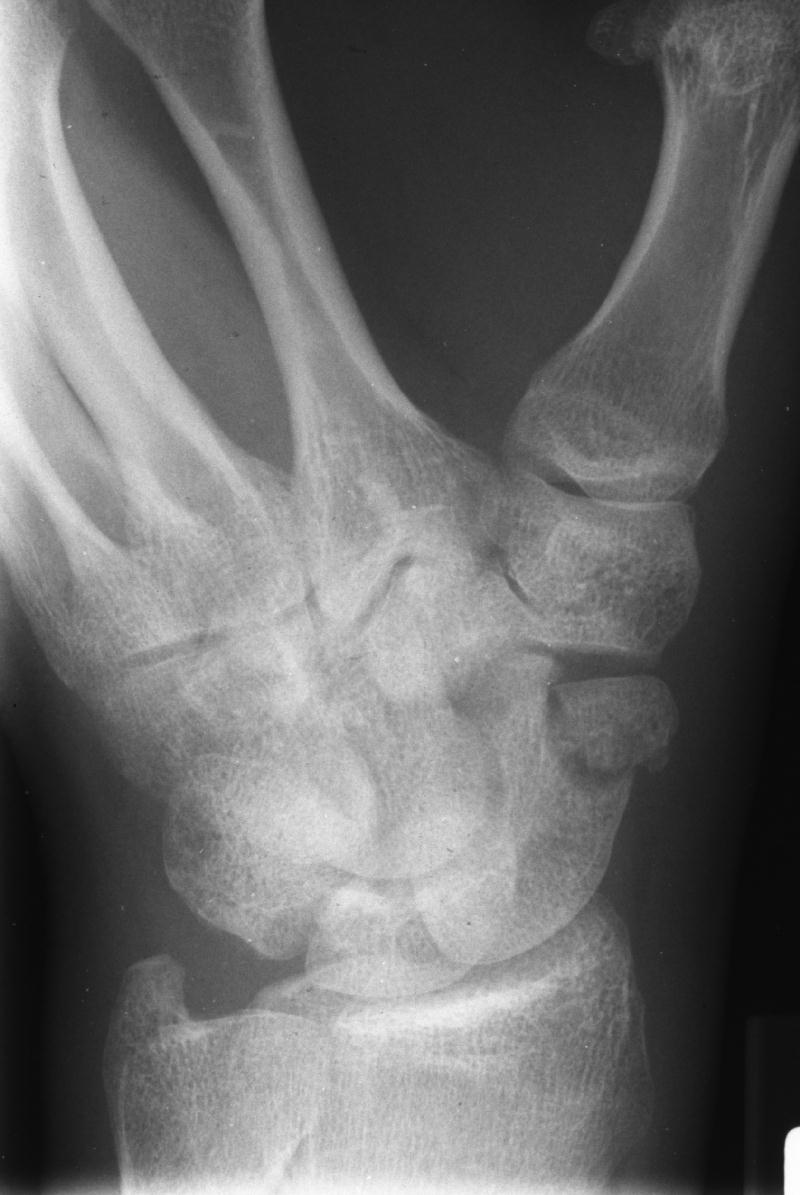

Clinical Example: Scaphoid Tubercle Fracture

scaphoid tubercle fracture